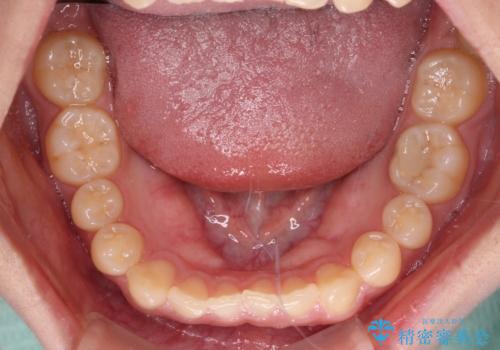

治療途中の奥歯と矯正治療の後戻り インビザライン・ライトによる矯正治療

- 根管治療を行ったままの奥歯と、矯正治療の後戻りを気にして来院された患者様です。

根管治療された歯に症状はなく、オールセラミッククラウンにて補綴治療を行うこととしました。

矯正治療の後戻りは軽微であったため、インビザラインの簡易パッケージであるインビザライン・ライトを用いて歯列を整えることとしました。

クラウンはよりよい咬み合わせで装着したいため、インビザラインを1セット使用して概ね歯列を整えた時点で補綴治療を行い、その後仕上げの矯正治療を行いました。